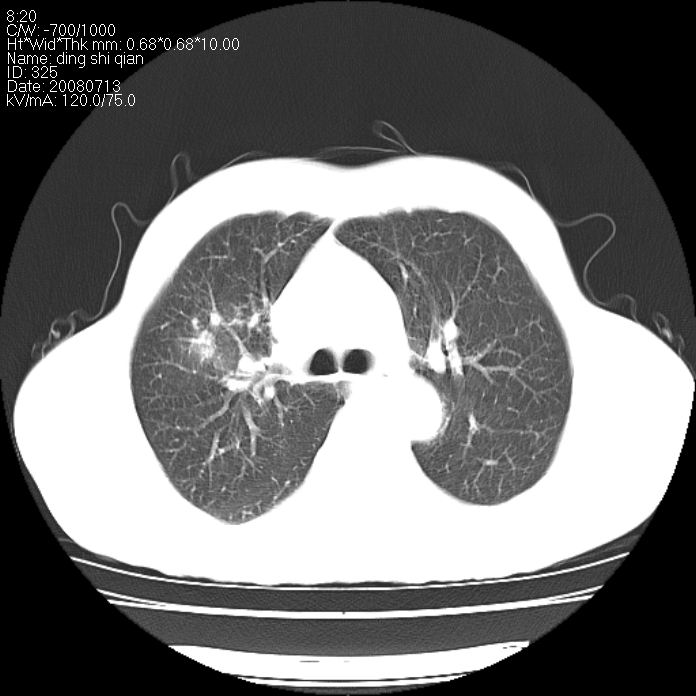

标题: CT14654:男 50岁 近来胸痛 [打印本页]

标题: CT14654:男 50岁 近来胸痛

右侧上肺块状软组织影,浅分叶,边缘毛刺证,与胸膜粘连,考虑:周围性肺癌

右肺上叶周围型肺癌可能性大。

右侧上肺块状软组织影,浅分叶,边缘毛刺证,与胸膜粘连,考虑:周围性肺癌!支持!

典型右肺周围型肺癌

右肺上叶周围型肺癌。